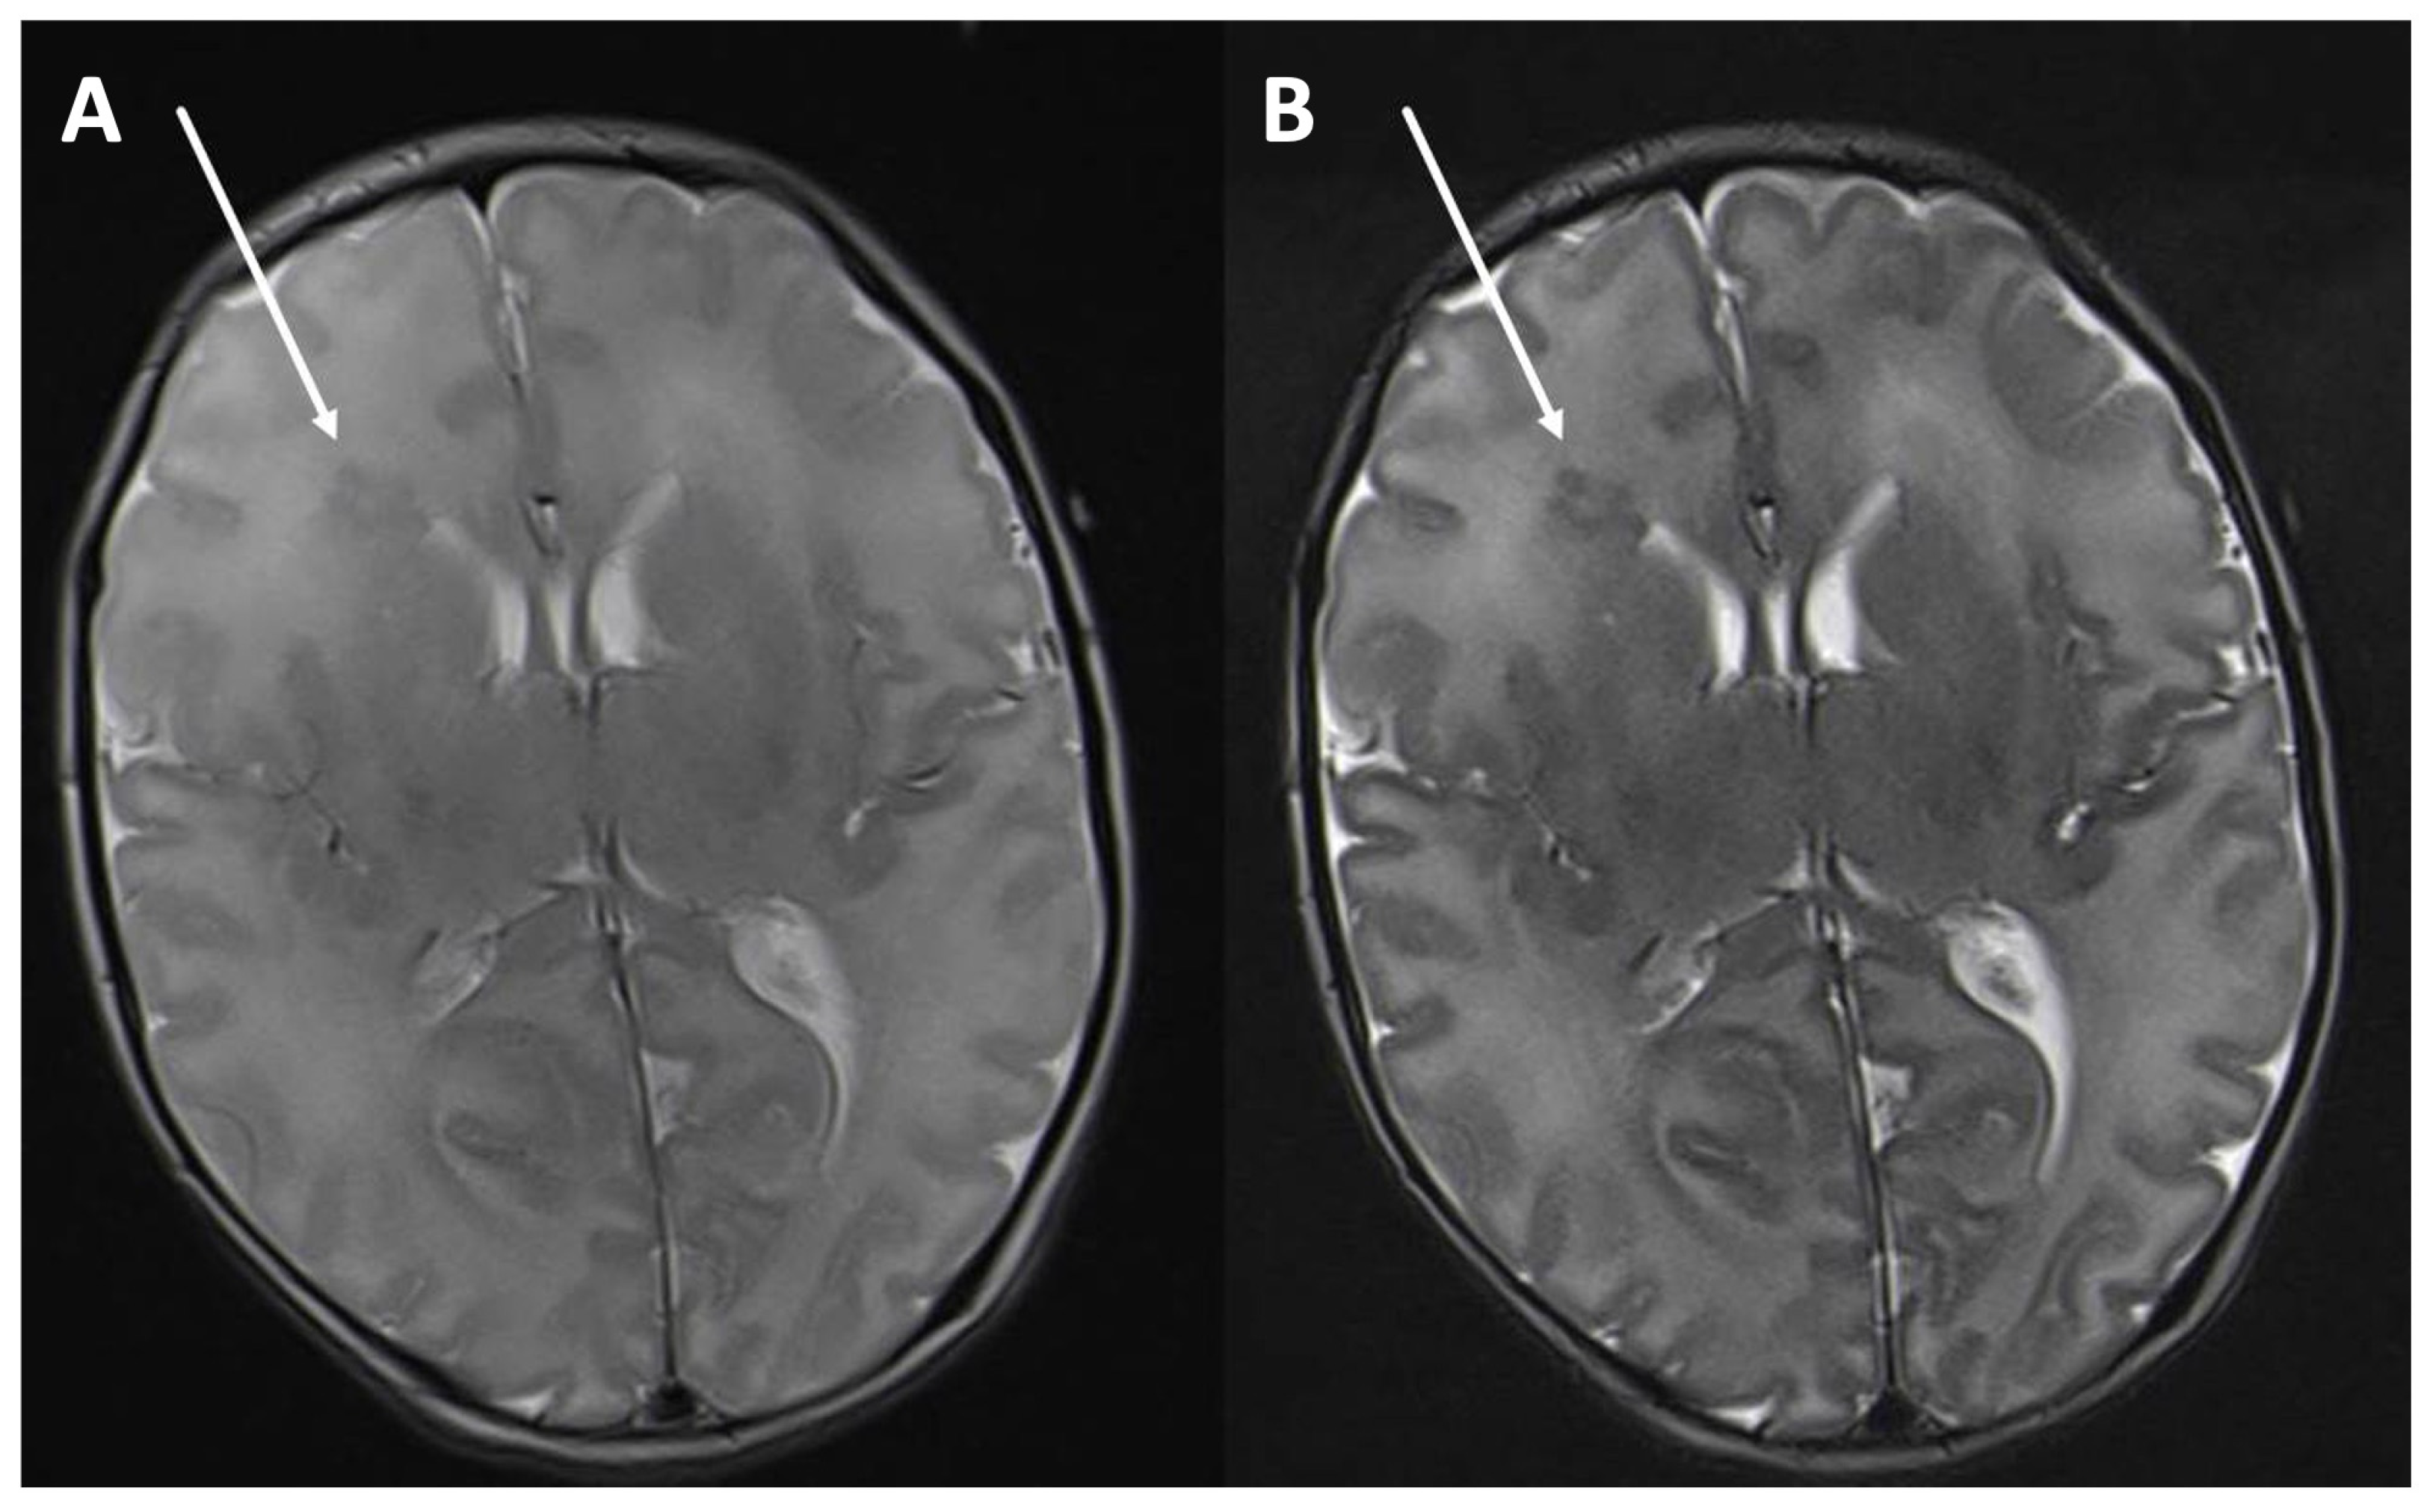

Figure 2.

T2-weighted image in an axial orientation of a two-week-old male with seizures. The periventricular right frontal heterotopia (arrow) can be seen more clearly with a longer echo time of 203 ms, TR 5500 (B) than with a medium echo time of 113 ms, TR 5500 (A).